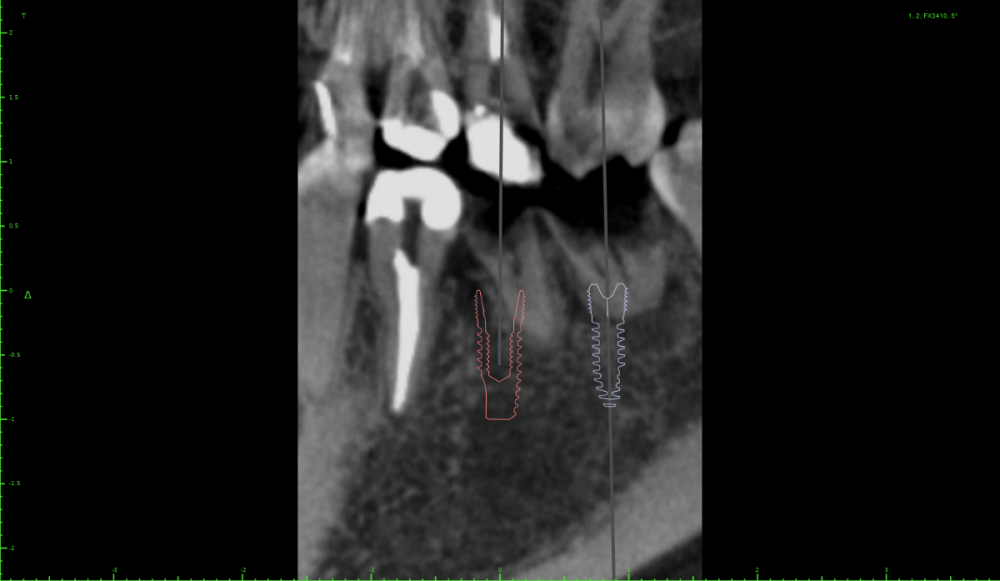

Евгений Ходыкин Опубликовано 23 июля, 2021 Поделиться Опубликовано 23 июля, 2021 @Женька шейка ниже жёлтой линии, которую нарисовали. 1 Ссылка на комментарий

Irouil Опубликовано 26 июля, 2021 Поделиться Опубликовано 26 июля, 2021 Я бы придал имплантам немного ангуляции Ссылка на комментарий

Женька Опубликовано 27 июля, 2021 Автор Поделиться Опубликовано 27 июля, 2021 30 минут назад, Евгений Ходыкин сказал: 2. Топить глубже. всё-таки я правильно понимаю, что у двух соседних имплантатов желательно размещать платформы на одном уровне? Ссылка на комментарий

Евгений Ходыкин Опубликовано 27 июля, 2021 Поделиться Опубликовано 27 июля, 2021 7 часов назад, Женька сказал: всё-таки я правильно понимаю, что у двух соседних имплантатов желательно размещать платформы на одном уровне? Не обязательно Ссылка на комментарий